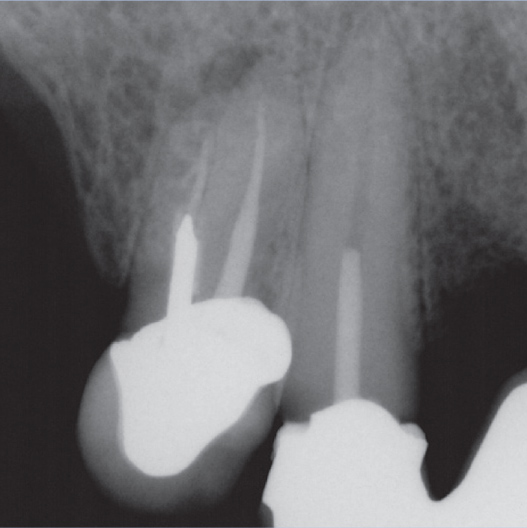

After

After Root Canal treatment